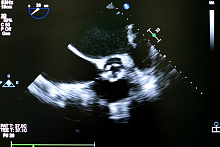

Сравнение транскатетерной и хирургической замены аортального клапана

Целью исследования PARTNER 3 было сравнить долгосрочную эффективность транскатетерной замены аортального клапана с хирургической заменой аортального клапана у пациентов с симптомным аортальным стенозом.